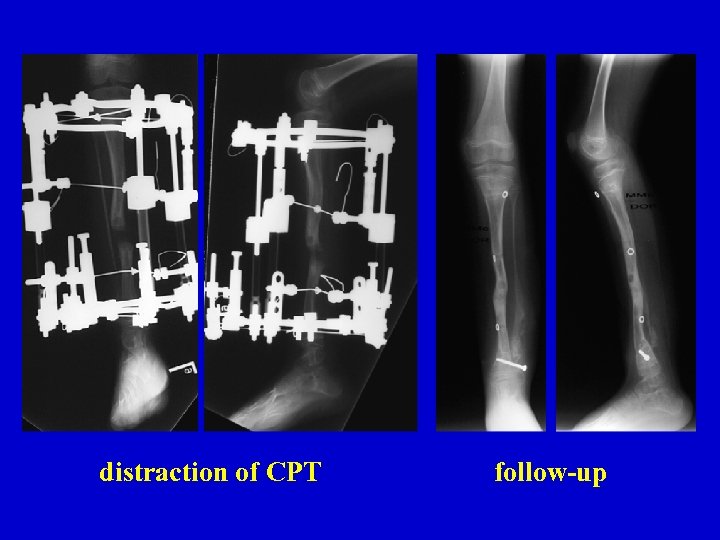

distraction of CPT follow-up

distraction of CPT follow-up